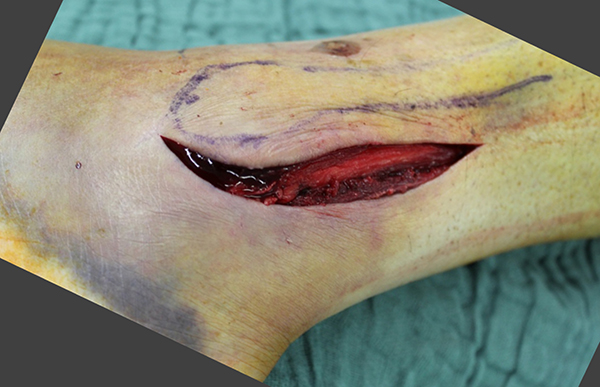

Luxationsfrakturen (Abbildung 7) sollten unter i.v.-Analgesie so schnell wie möglich reponiert werden, um Haut- und Weichteilschäden, Störungen der Durchblutung und Sensibilität, sowie den durch die Fehlstellung bedingten Druck auf den Knorpel zu verringern. Anschließend erfolgt die Ruhigstellung in einem gespaltenen Unterschenkelgips. Offene Frakturen, geschlossene Frakturen mit kritischen Weichteilverhältnissen, sowie hochgradig instabile Frakturen, die sich unter entsprechender Analgesie nicht zufriedenstellend reponieren bzw. retinieren lassen, stellen eine Notfallindikation dar. In diesen Fällen sollte die Anlage eines Fixateur externe erfolgen (Abbildung 8). Die definitive Frakturversorgung erfolgt zweizeitig nach entsprechender Konsolidierung der Weichteile. Eine Kompartment-Spaltung ist bei OSG-Frakturen nur sehr selten erforderlich.